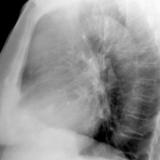

Thymic carcinoma Lat

Date: 08/15/2012

Views: 10105